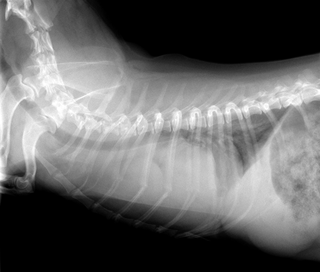

右心房血管肉腫(RA・HSA)

右心耳に発生する血管肉腫では右肋間開胸術(状況により正中切開術)により、心拍動下で心タンポナーデをおこしている心臓にアプローチ。